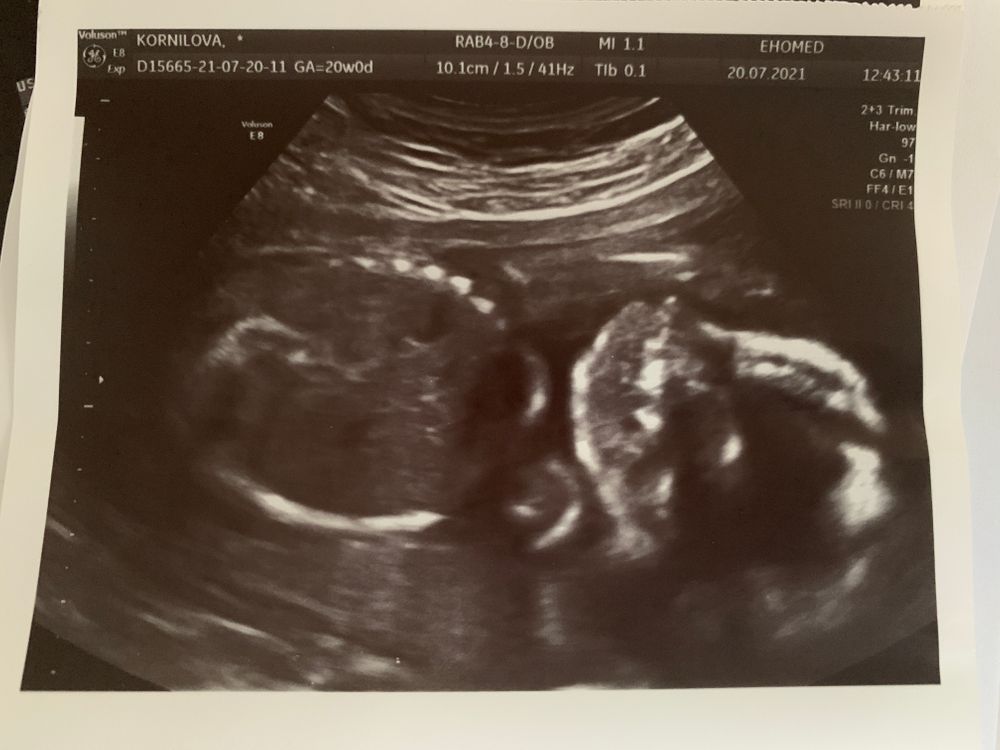

2 скрининг. Низкая плацента. Тонус

ТонусСегодня было второе узи. Мы ждём девочку🥰. С малышкой все хорошо, никаких отклонений. Плацента немного поднялась (с 16 мм до 19 мм), но всё-таки низко.

Уже неделю мучает тонус, горбок появляется то слева то справа то по центре. Фото: